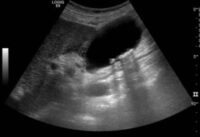

Im Längsschnitt über die Gallenblase erkennt man anstelle eines glatt begrenzen Gallenblasenlumens eine unregelmäßig begrenzte echoarme Flüssigkeitsansammlung im Gallenblasenbett und ventral der Leber. Es handelt sich hier um eine perforierte akute Cholecystitis auf Basis einer Cholecystolithiasis, welche bereits nach einer kurzen Schmerzperiode von 48h eingetreten ist. Eine solche Komplikation kann durch eine rasche Sonographie und anschließende chirurgische Vorstellung vermieden werden.